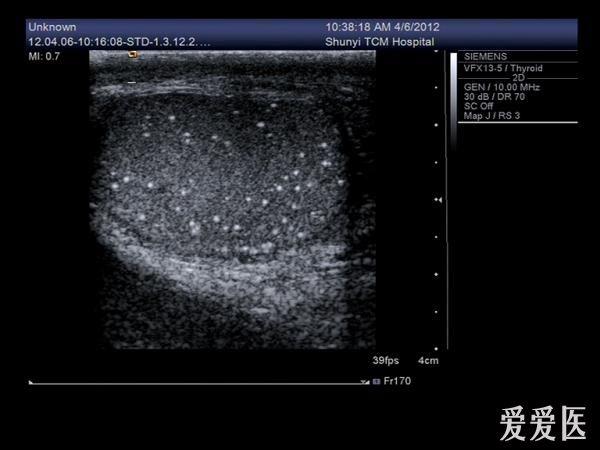

睾丸内点状强回声是什么东西?有图

前几天有个病人来检查,说睾丸疼,大小、形态都没什么变化,就是睾丸内有好多点状强回声,伴彗星尾征。请问这些东西是什么?钙化点?

典型的睾丸微石症

典型的睾丸微石症,有些人和结核有关系!